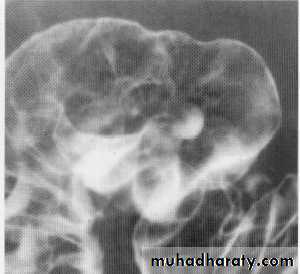

Exophytic tumor